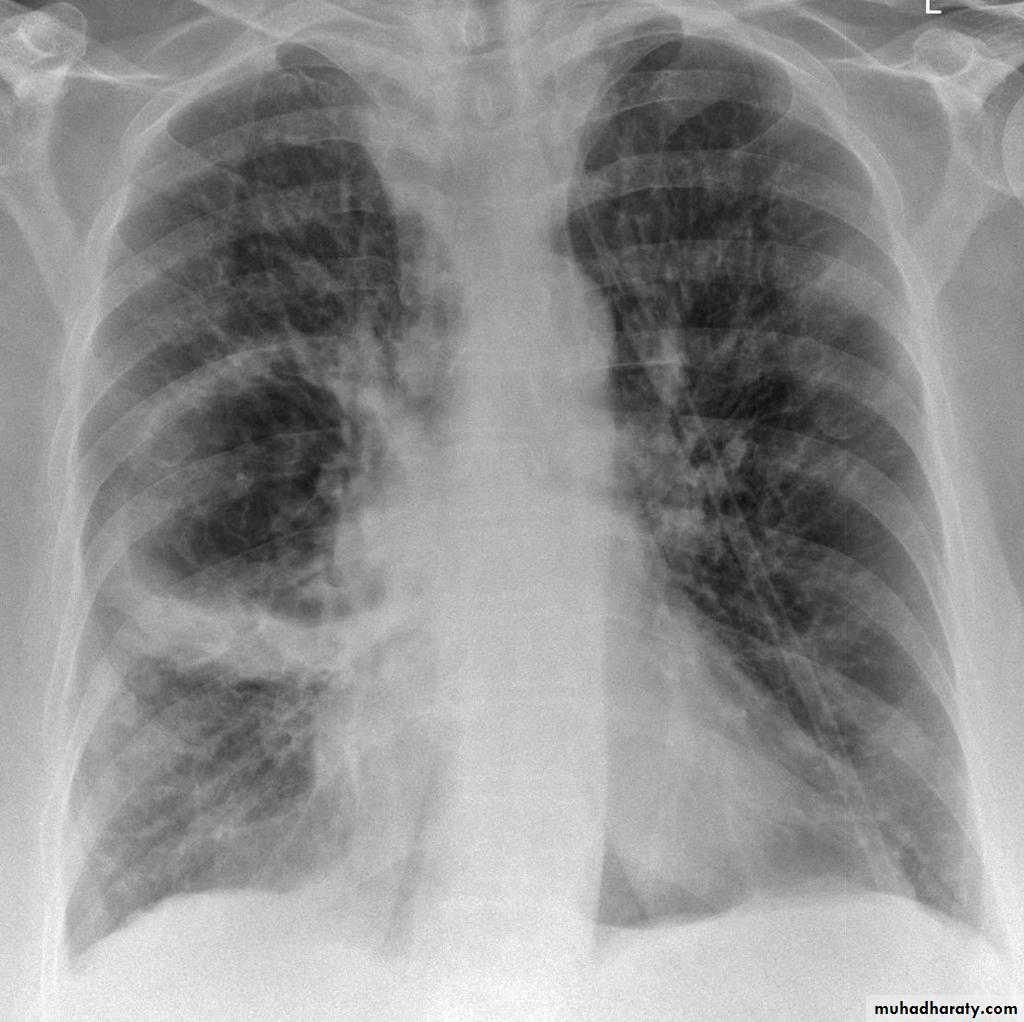

Lobular consolidation ( broncho pneumonia )

Very important to consider that pulmonary edema in normal sized heart have close similar appearance to broncho pneumonia

The important Golden Key differentiation is the cardiac size being enlarged in pulmonary edema .

Post primary TB broncho pneumoniacotton wool sign

Post primary TB Bronch pneumonia

Q ???? Be careful in description & DxBoth of them have similar appearance of broncho pneumonic shadow

??????What is being the pit fall in such films ???

Who can you differentiate ???